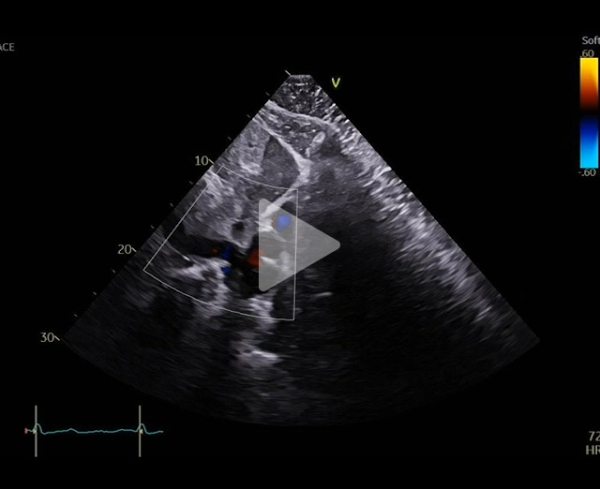

Vidéo 4

FEVG 30% , hypokinésie diffuse, pas de valvuloptahie aortique ni mitrale. VD non dilaté, normokinétique avec IT modérée. Prothèse en place avec passage de bulles résiduelles modéré. Sonde de DAI semblant extrêmement mobile.

Au cours du suivi, réapparition d’une dyspnée, se majorant progressivement jusqu’au stade 3 de la classification NHYA avec nouvelle ETT au mois d’aout 2025.

FEVG 35%, hypokinésie diffuse, pas de valvulopathie aortique ni mitrale.

VD non dilaté, normokinétique mais IT désormais laminaire avec reflux dans les veines sus hépatiques.